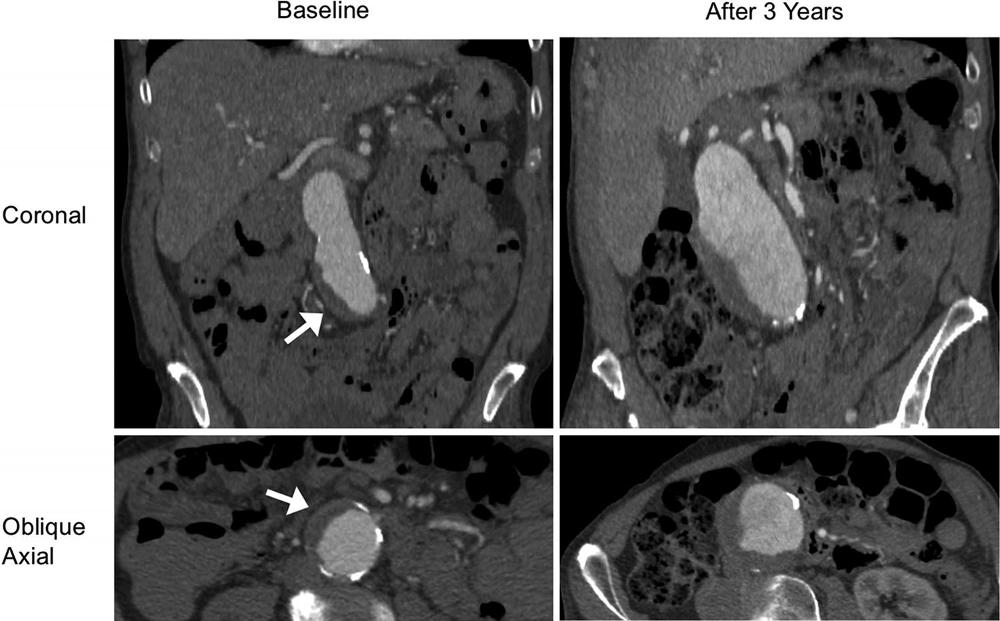

Figure 4. A patient (aged 85 years, male) with a fast-growing abdominal aortic aneurysm with intraluminal thrombus at baseline. Contrast-enhanced CT images (coronal and oblique axial planes) show that the aneurysm grew from 4.1 to 6.3 cm within 3 years at a growth rate of 7.3 mm/y. Arrow shows the intraluminal thrombus.

High-res (TIF) version